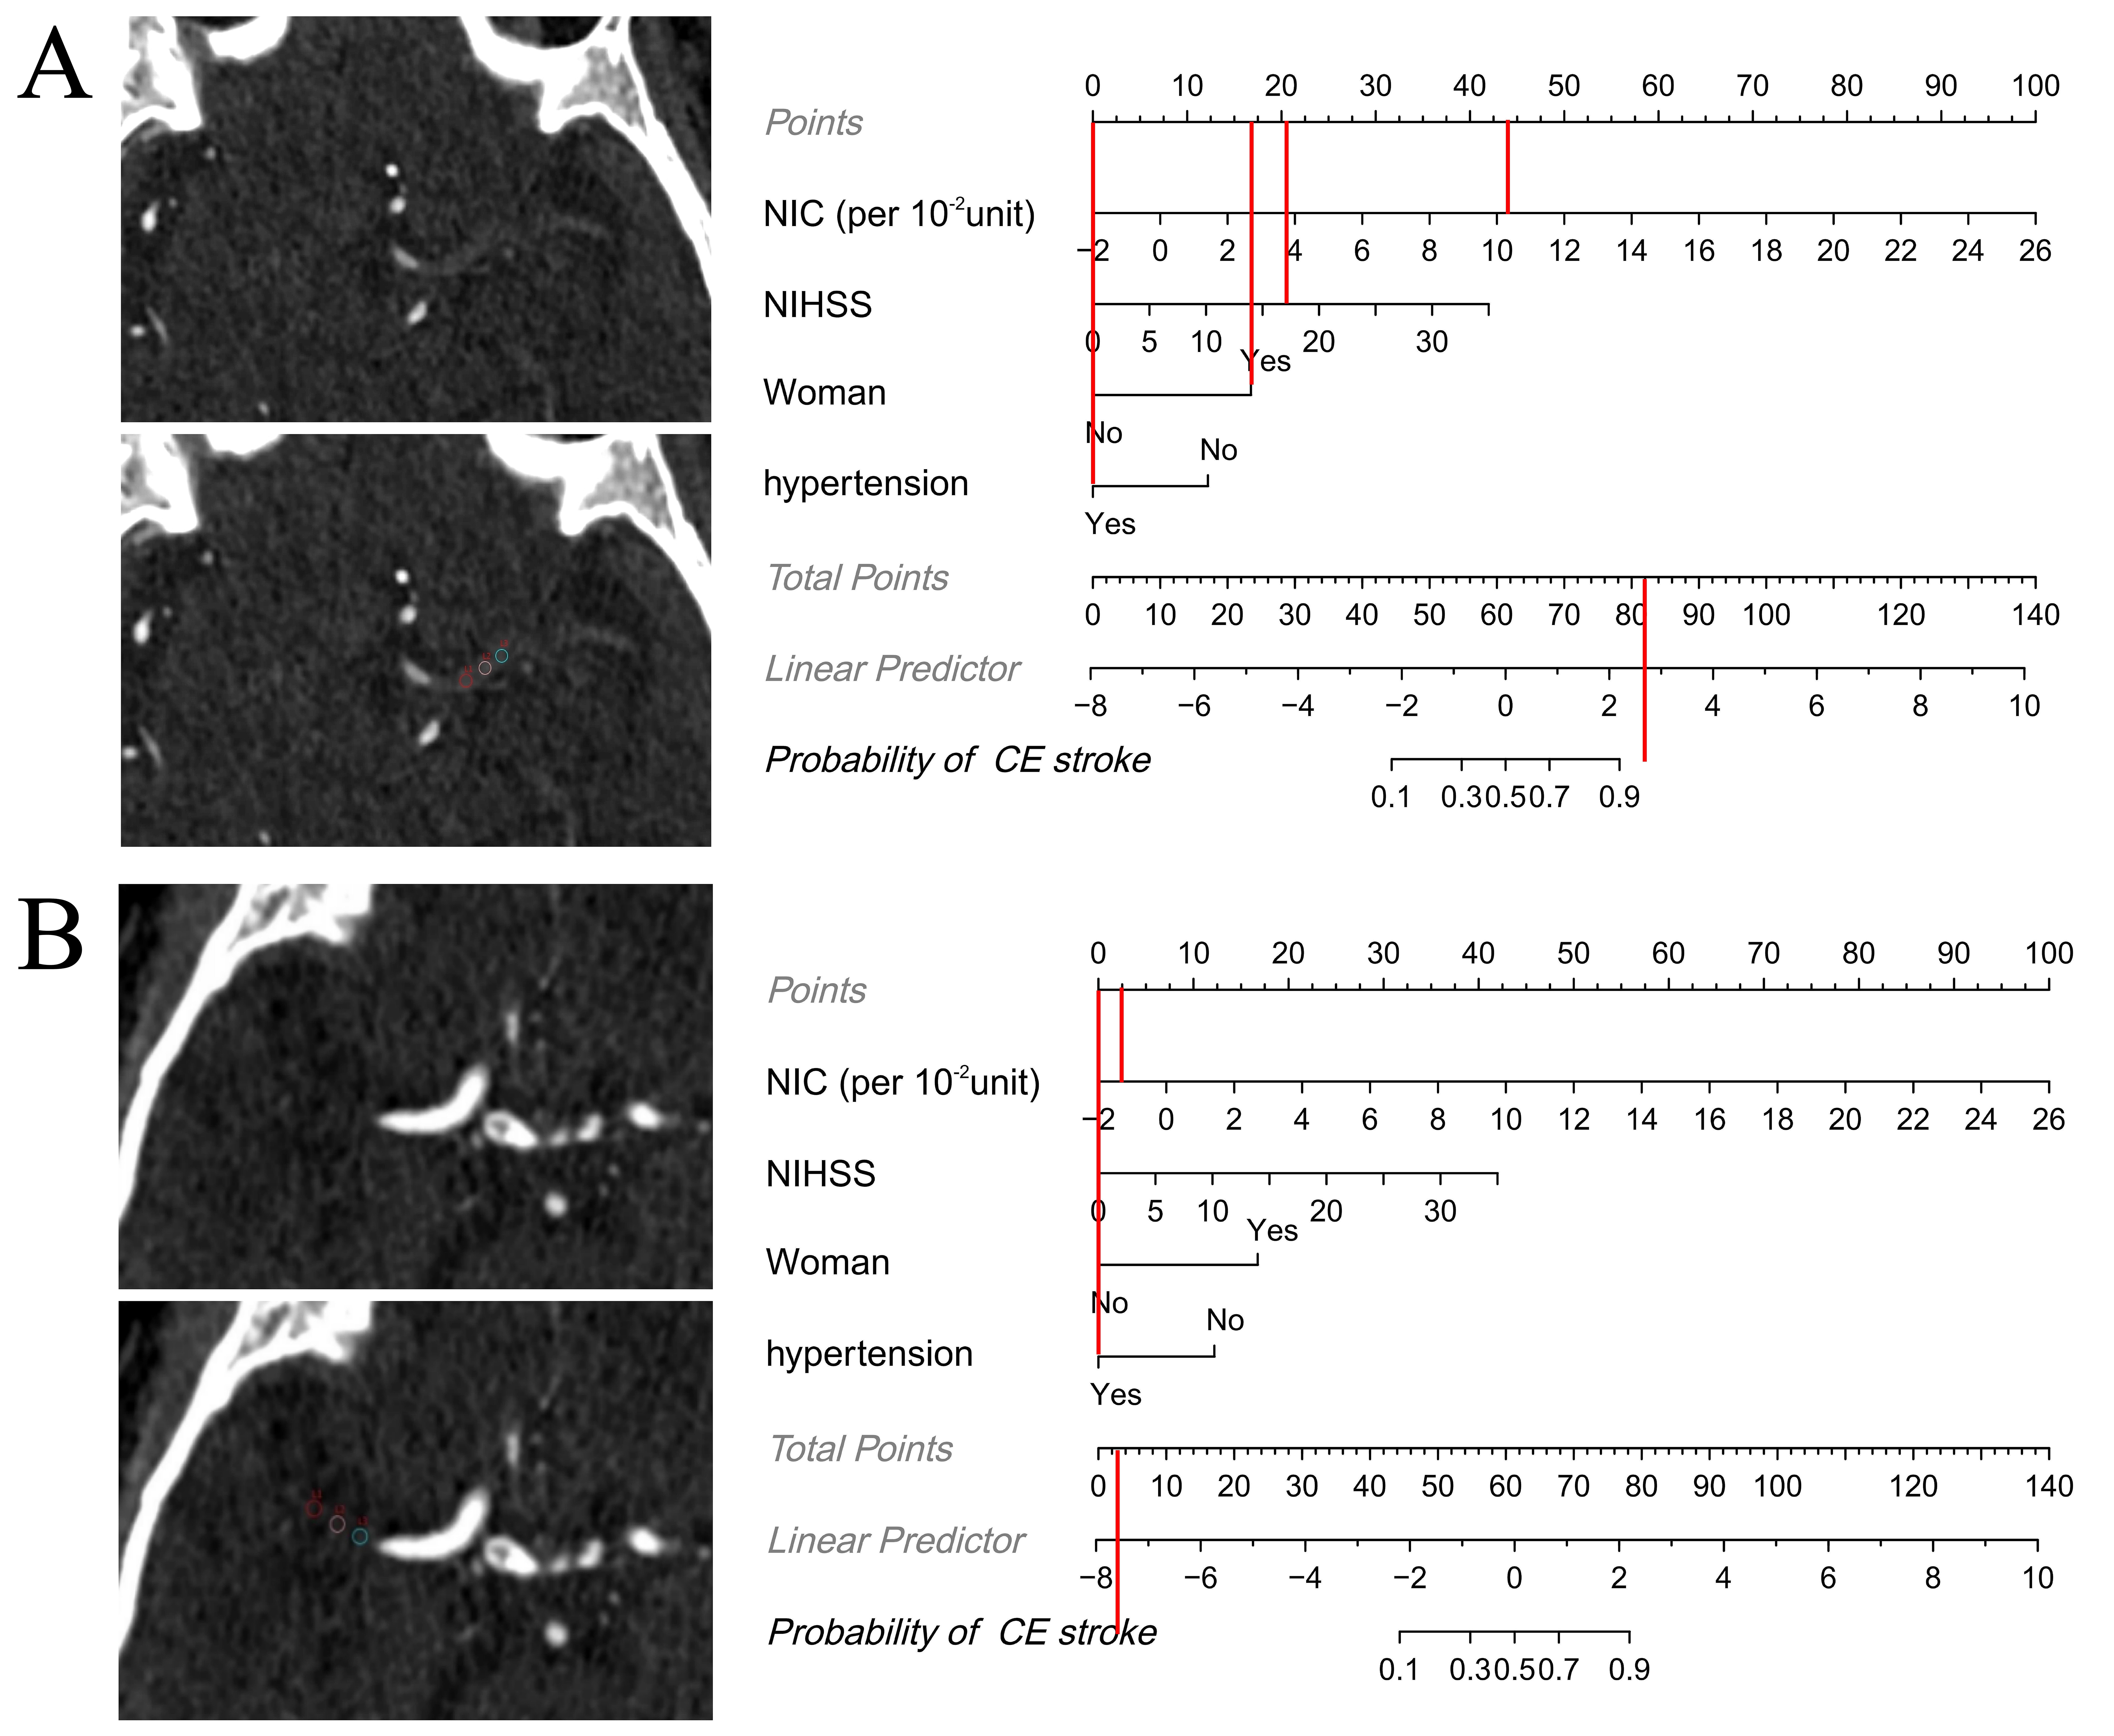

Fig. 6. Examples showing how the nomogram can be applied in clinical practice. The figures demonstrate the step-by-step process of computing the probability of cardioembolic (CE) stroke using the nomogram. (A) Axial iodine overlay maps in a 77-year-old woman with a National Institutes of Health Stroke Scale (NIHSS) level of 17 at admission. Normalized iodine concentration (NIC) (per 10-2 unit) = 10.2, hypertension = “yes”. The total score was 82, which maps to a CE stroke probability of greater than 0.9. The patient had a CE stroke according to Trial of Org 10172 in Acute Stroke Treatment (TOAST), which was consistent with the nomogram result. (B) Axial iodine overlay maps in a 56-year-old man with a NIHSS level of 0 at admission. NIC (per 10-2 unit) = –1.4, hypertension = “yes”. The total score was 2.5, which maps to a CE stroke probability of less than 0.1. The patient had an atherosclerotic (LAA) stroke according to TOAST, which was consistent with the nomogram result.